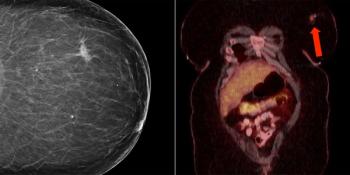

A 57-year-old woman with a history of stage IIB breast cancer (ypT2N1M0) status post neoadjuvant chemotherapy and left partial mastectomy presents to the radiation oncology clinic for CT simulation in preparation for breast radiotherapy. Noncontrast CT scan incidentally found the abnormality depicted with arrows below. What is your diagnosis?